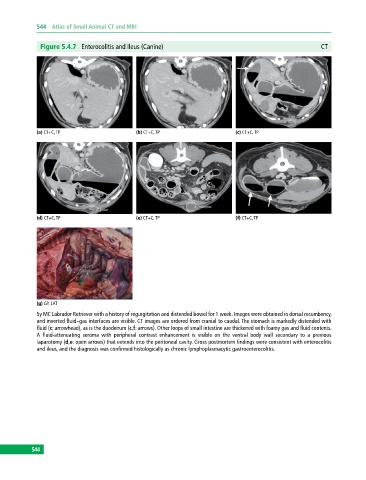

Figure 5.4.7 Enterocolitis and Ileus (Canine) CT

(a) CT+C, TP (b) CT+C, TP (c) CT+C, TP

(d) CT+C, TP (e) CT+C, TP (f) CT+C, TP

(g) GP, LAT

5y MC Labrador Retriever with a history of regurgitation and distended bowel for 1 week. Images were obtained in dorsal recumbency,

and inverted fluid–gas interfaces are visible. CT images are ordered from cranial to caudal. The stomach is markedly distended with

fluid (c: arrowhead), as is the duodenum (c,f: arrows). Other loops of small intestine are thickened with foamy gas and fluid contents.

A fluid‐attenuating seroma with peripheral contrast enhancement is visible on the ventral body wall secondary to a previous

laparotomy (d,e: open arrows) that extends into the peritoneal cavity. Gross postmortem findings were consistent with enterocolitis

and ileus, and the diagnosis was confirmed histologically as chronic lymphoplasmacytic gastroenterocolitis.